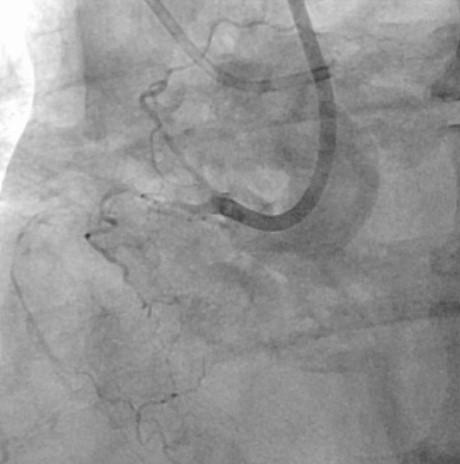

患者的左边血管堵塞也极其严重,主干道狭窄99%,合并钙化、弥漫、分叉,在预扩张球囊呈现明显的“腰征”的情况下,罗裕主任果断选择了旋磨治疗,1.5mm的磨头5次后通过,最后成功植入两枚支架。

左图术前左冠,右图术后左冠

手术历经近3小时,同台对患者右冠、左冠进行了完全血运重建。在ECMO的支持下,患者生命体征平稳,手术顺利,病人安返监护病房。术后生命体征稳定,当日ECOM即停机,近日患者已康复出院。